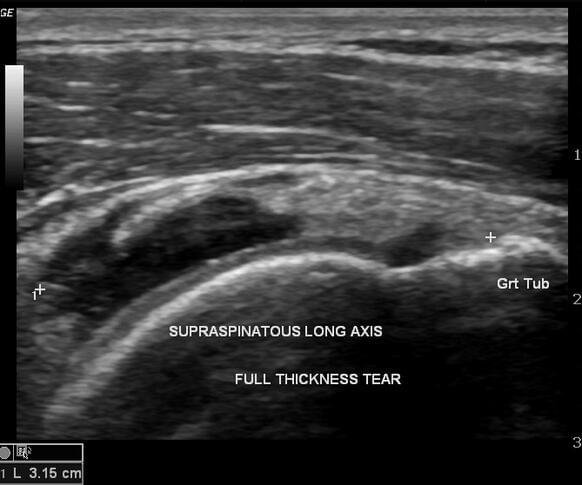

A full thickness tear of the supraspinatus tendon occurs when the rupture extends through the entire thickness of the tendon, creating a communication between the shoulder joint and the subacromial space.

These injuries are considered an advanced form of supraspinatus tendon tear and may vary in severity. They are often divided into:

- Incomplete full-thickness tear, where only a small part of the tendon is detached from the bone.

- Complete full-thickness tear, in which the tendon is fully detached from its insertion on the humerus.

- Ultrasound is commonly used as an initial imaging method because it allows dynamic assessment of the rotator cuff tendons and can reliably detect partial and full-thickness tears.